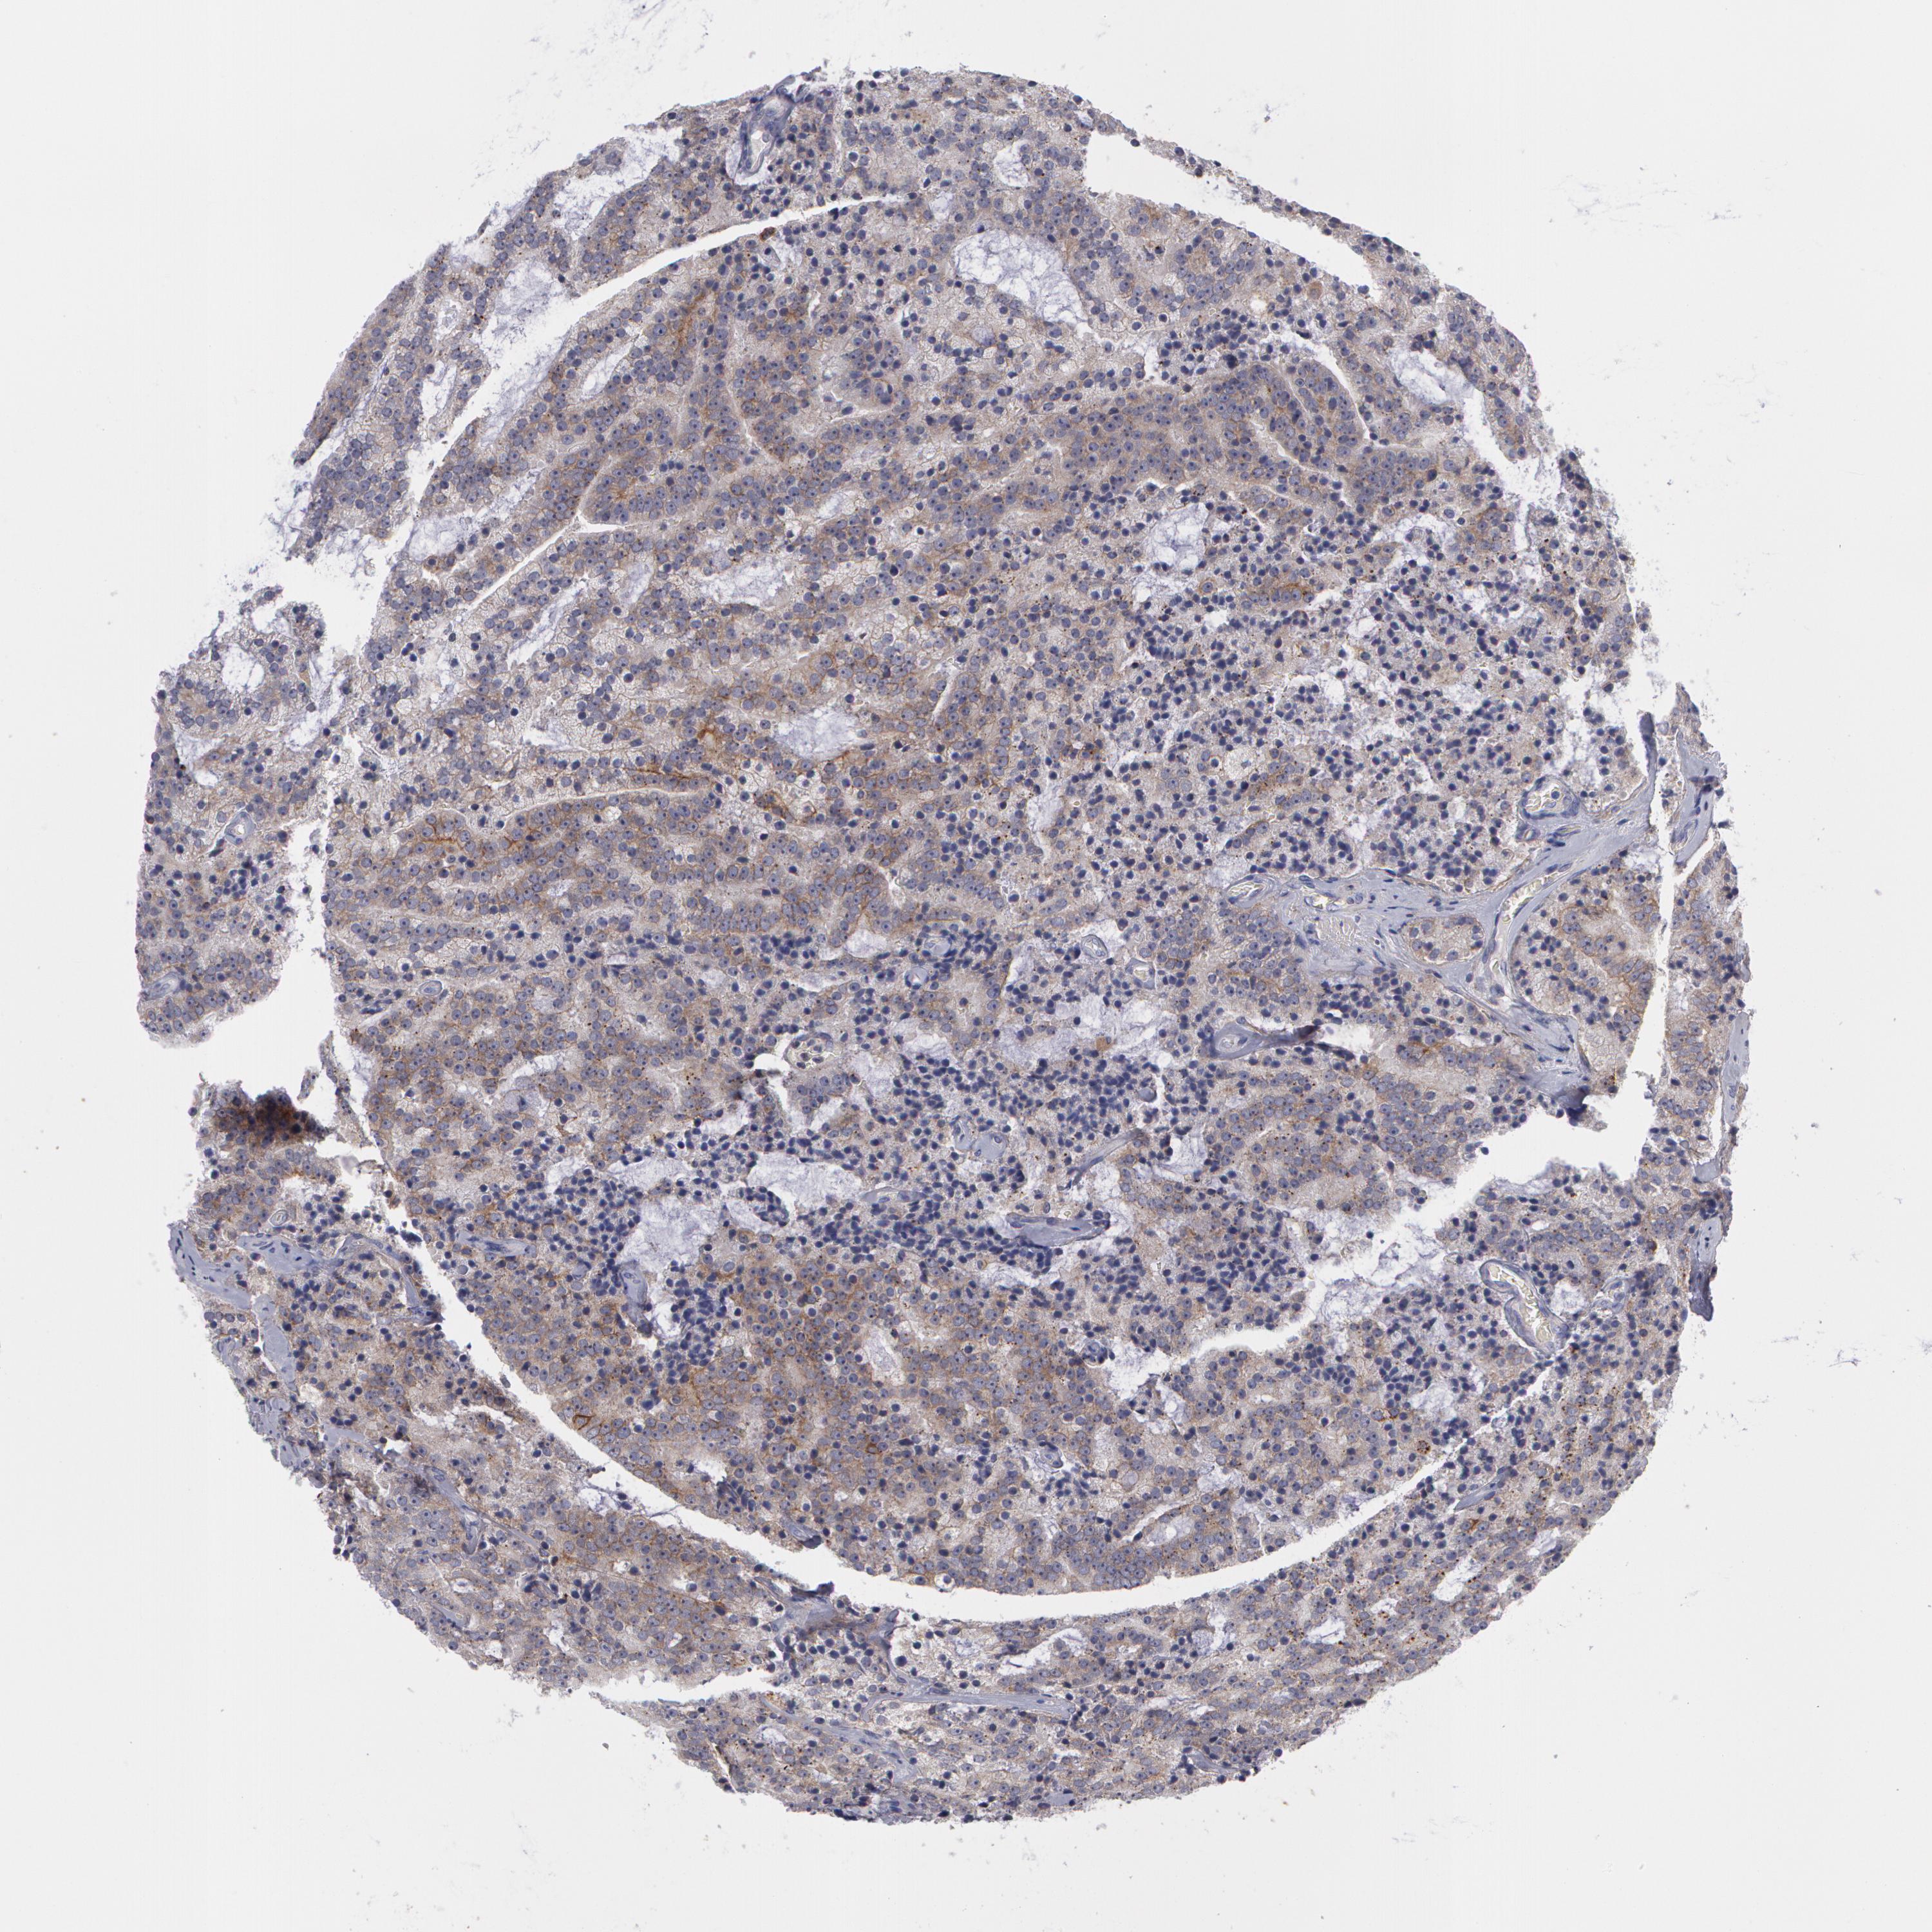

PROSTATE CANCER - Protein expressioni

A mouse-over function shows sample information and annotation data. Click on an image to view it in a full screen mode. Samples can be filtered based on level of antibody staining by selecting one or several of the following categories: high, medium, low and not detected. The assay and annotation is described here.

Note that samples used for immunohistochemistry by the Human Protein Atlas do not correspond to samples in the TCGA dataset.

Antibody stainingi

Antibody staining in the annotated cell types in the current human tissue is reported as not detected, low, medium, or high, based on conventional immunohistochemistry profiling in selected tissues. This score is based on the combination of the staining intensity and fraction of stained cells.

Each image is clickable and will lead to virtual microscopy that enables deeper exploration of all samples and also displays staining intensity scores, fraction scores and subcellular localization as well as patient and tissue information for each sample.

Antibody HPA001383

Antibody CAB000043

Antibody CAB020416

Antibody CAB062555

Adenocarcinoma, Medium grade

Adenocarcinoma, Low grade

Adenocarcinoma, High grade

Adenocarcinoma, NOS